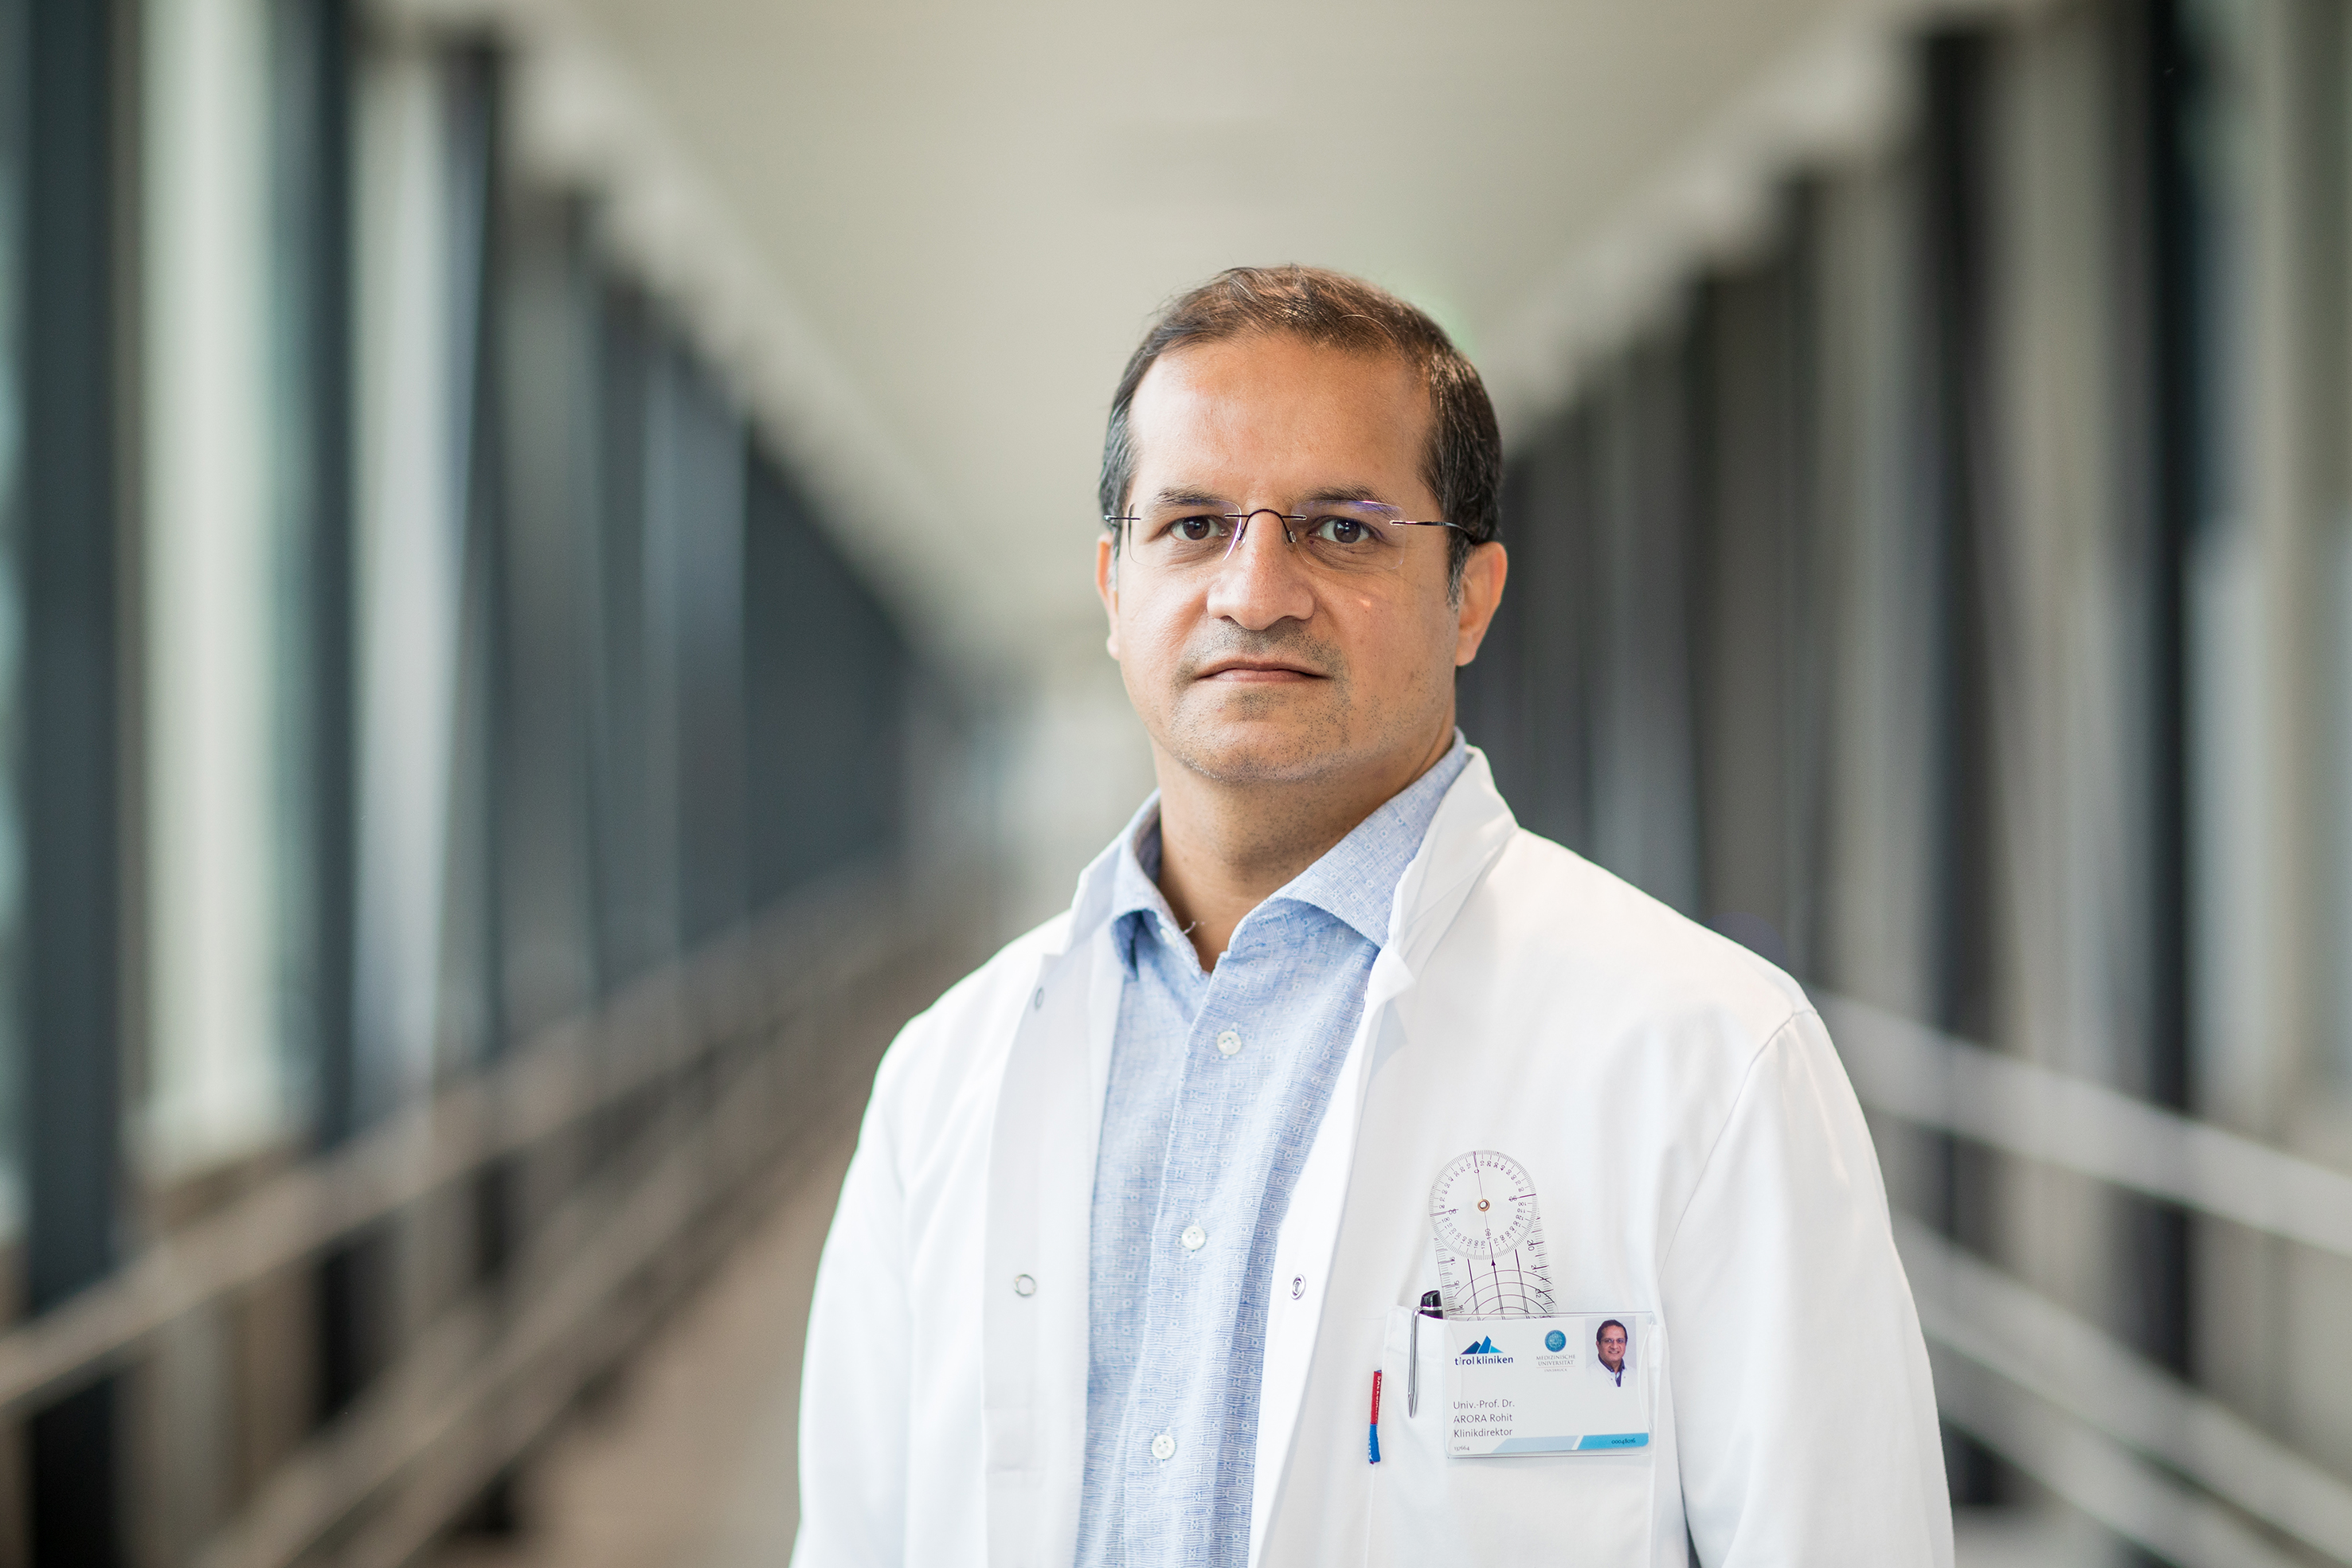

Zusammenlegung, neues Unfallmuster und Covid-19: Herausforderungen in der Traumatologie und Orthopädie

23.02. 07/2021

23.02. 07/2021

Periodische Fiebersyndrome

19.02. 06/2021

19.02. 06/2021

Aktuelle Entwicklungen an der Univ.-Klinik für Orthopädie und Traumatologie in Innsbruck